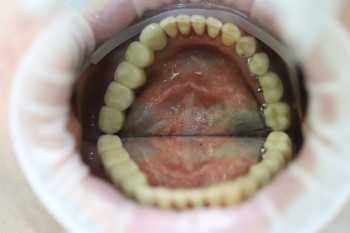

2 работы в портфолио